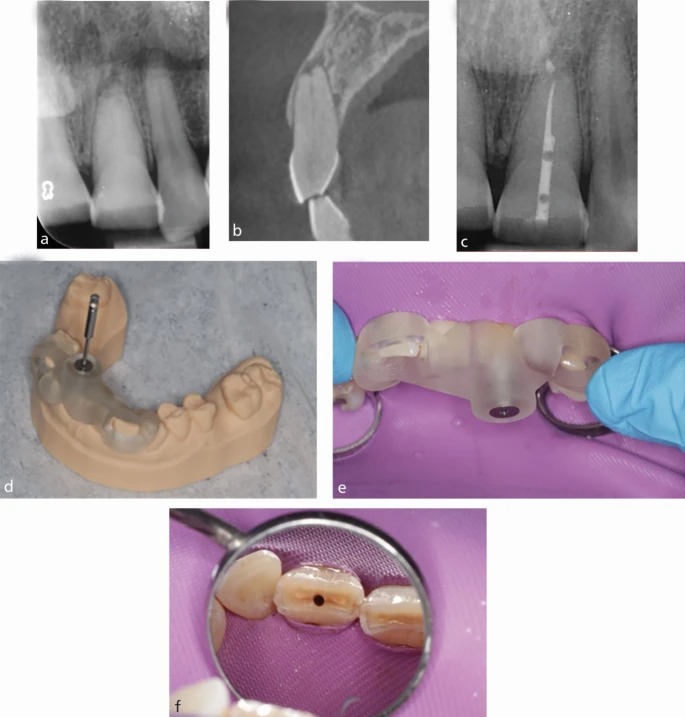

Клинический пример. Пациент мужского пола, около 50 лет, был направлен с жалобами на зуб 21.

a) Прицельная рентгенограмма зуба 21 показывает признаки апикальной патологии при непросматриваемом канале.

b) Сагиттальный срез КЛКТ выявляет проходимый канал и очаг воспаления в апикальной области зуба 21.

c) Послеоперационная прицельная рентгенограмма после эндодонтического лечения: заметны небольшие пустоты в реставрации полости доступа, что обусловлено крайне консервативным дизайном доступа.

d) 3D-печатный навигационный шаблон, полностью установленный на модель. Обратите внимание на контрольные окна, позволяющие убедиться в плотной посадке шаблона.

e) Полная посадка шаблона подтверждена через контрольные окна.

f) Полость доступа, сформированная титановым бором Steco, показана после завершения навигационной процедуры.

Рентгенограмма выявила облитерацию пульпарного пространства и очаг апикальной патологии (см. рис. 9a). CBCT показала сохранённое пространство канала в корональной трети корня (рис. 9b). На основании данных томографии был изготовлен навигационный шаблон, с помощью которого удалось точно выйти на канал и провести эндодонтическое лечение с минимальной инвазией.

Применение навигационного шаблона в клиническом случае

После получения интраорального скана данные были импортированы в программу coDiagnostiX (Германия), где на основе совмещения с КЛКТ был спроектирован навигационный шаблон (рис. 9с). На виртуальной модели определили траекторию доступа таким образом, чтобы кончик титанового бора располагался параллельно длинной оси зуба и направлялся точно к предполагаемому устью канала (рис. 9d).

После окончательной проверки проекта шаблон был 3D-напечатан и установлен в полости рта пациента.

Под инфильтрационной анестезией и изоляцией коффердамом шаблон прочно зафиксировали на зубах. Через направляющую втулку проводили титановый бор Steco (Ø 1 мм, Германия), закреплённый в медленно вращающемся наконечнике (10 000 об/мин).

Работа велась короткими поступательными движениями («пампинг») до момента, когда канал можно было зондировать ручным файлом малого размера. После извлечения шаблона и подтверждения прохождения канала лечение было завершено по стандартному протоколу. На рисунке 9f показан размер сформированной полости доступа, а на рисунке 9e — послеоперационная рентгенограмма.